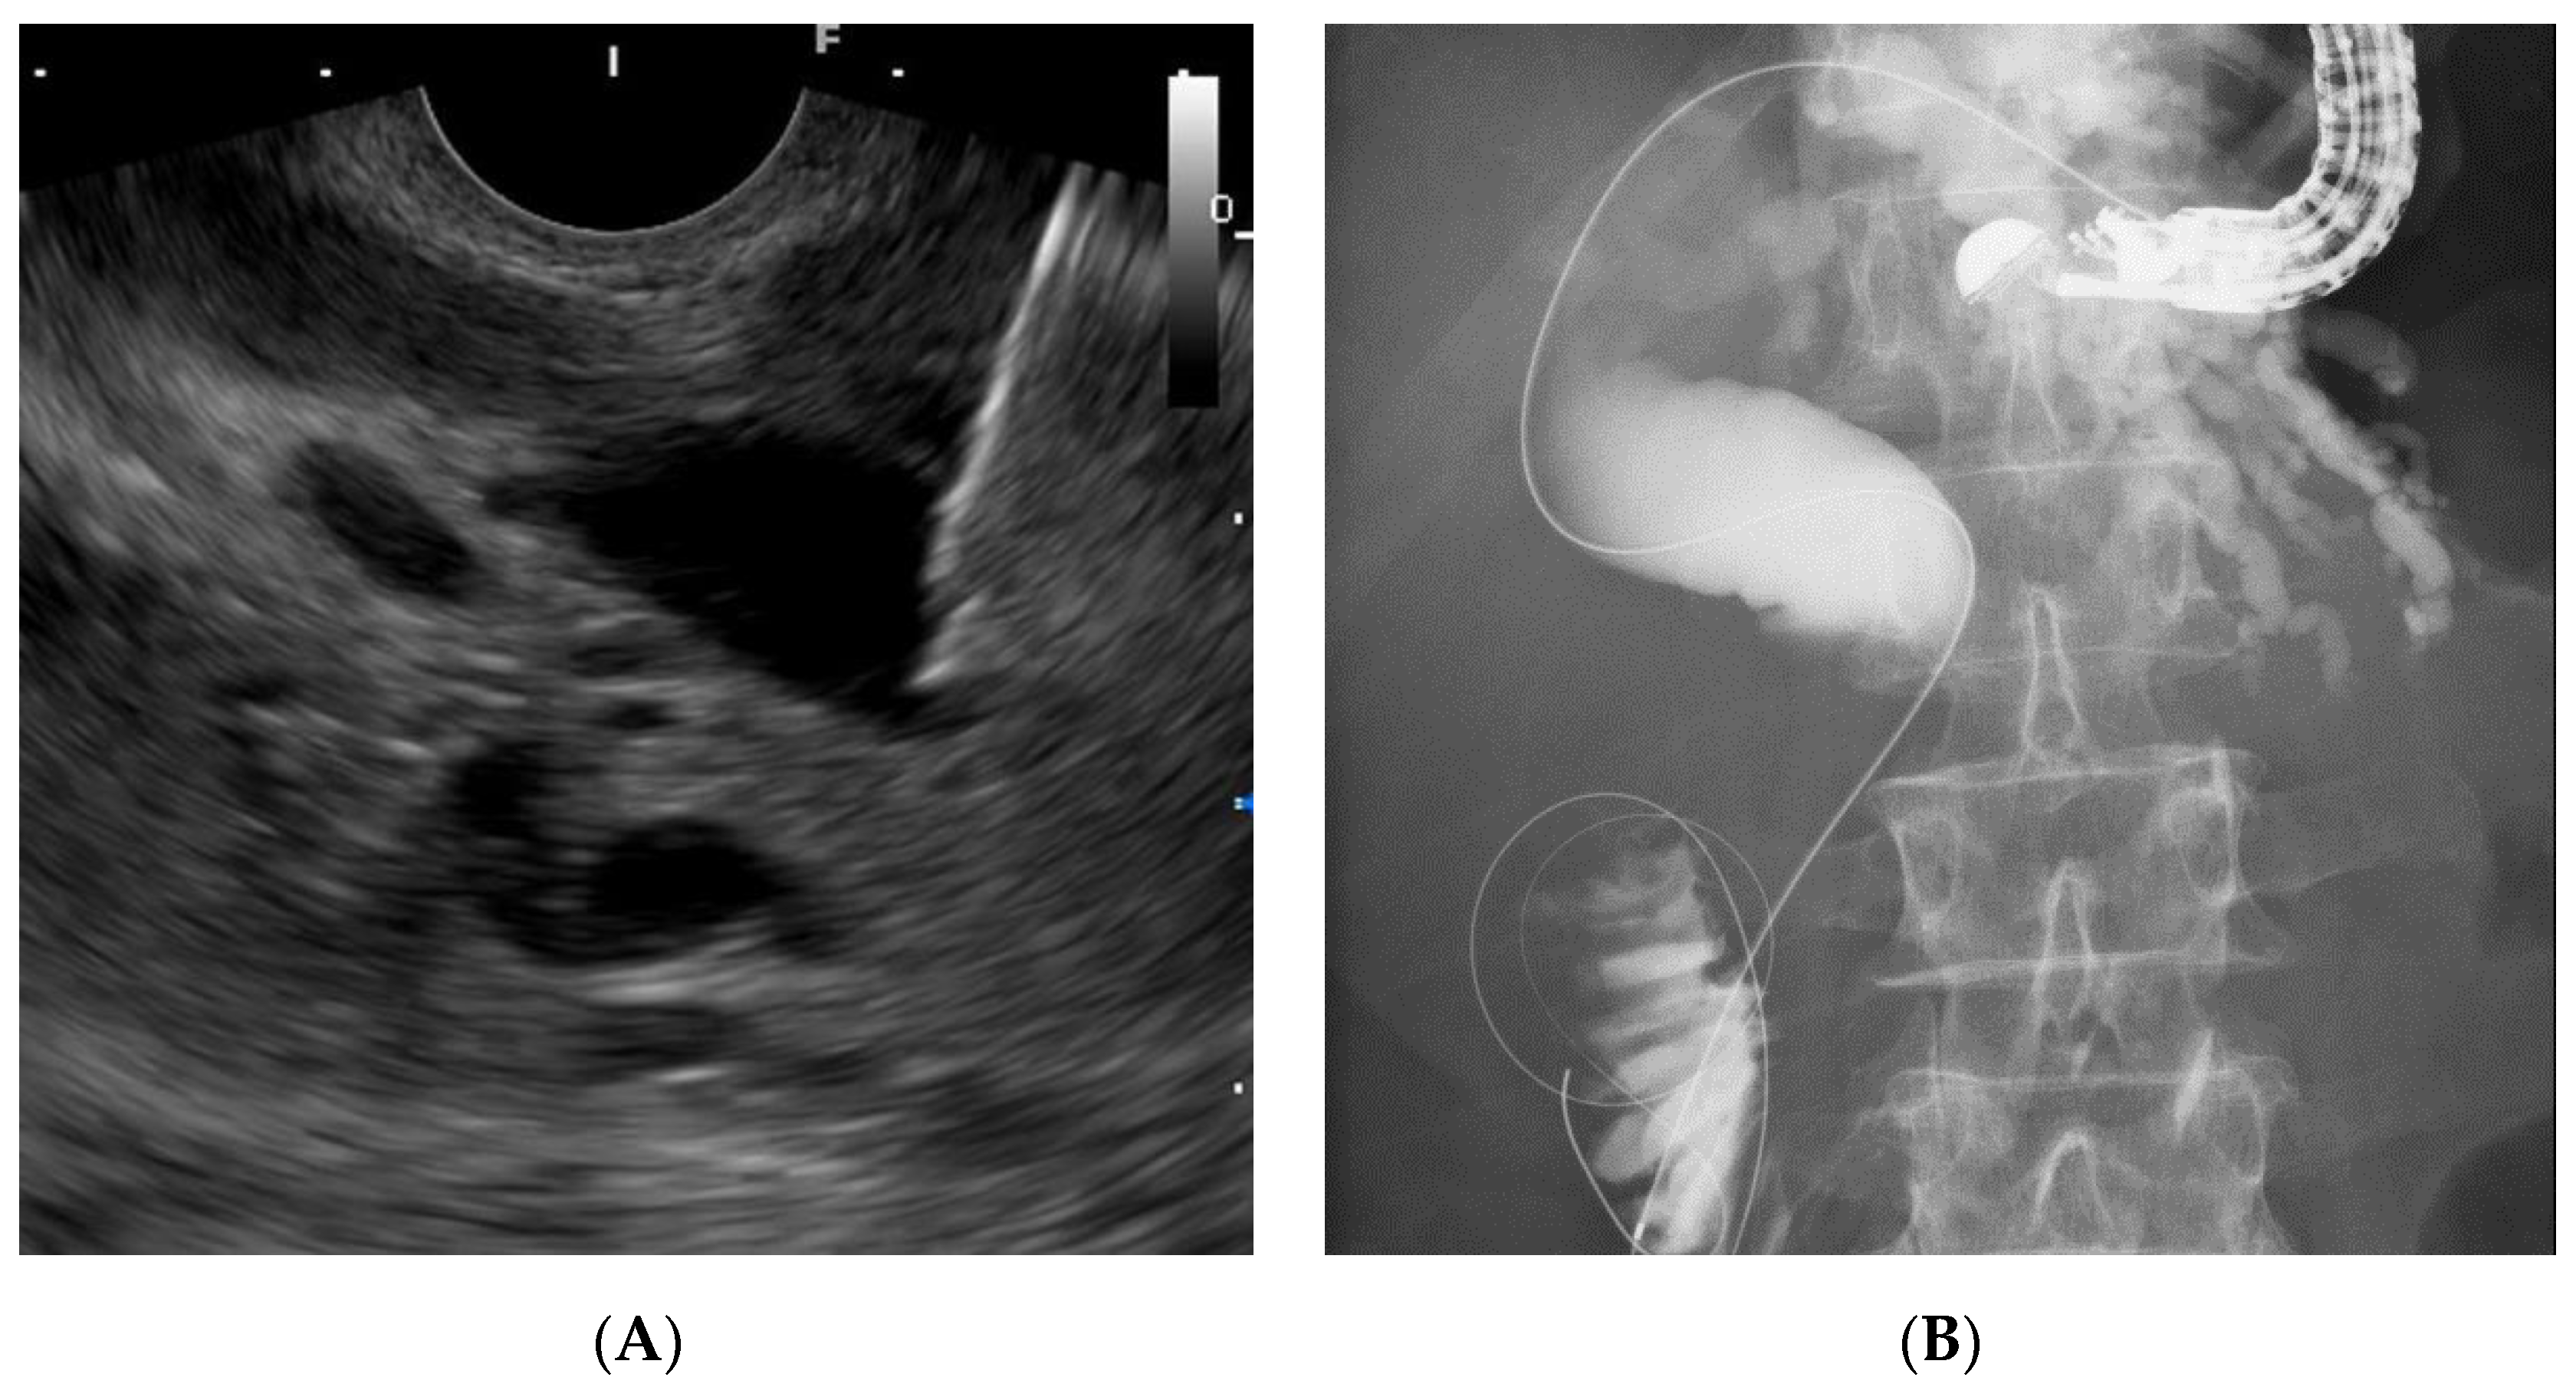

2.3. EUS-RV Procedure

2.4. Our EUS-RV Method Regarding Approach Routes and Needle Sizes

2.5. Biliary Cannulation Methods during EUS-RV